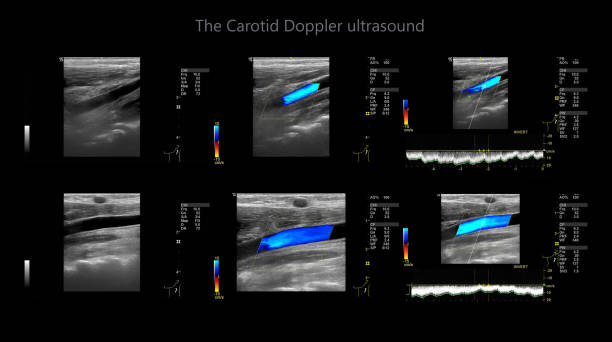

경동맥 초음파 검사의 원리

경동맥 초음파 검사는 초음파 기계를 사용하여 경동맥의 상태를 확인하는 검사입니다. 이 검사는 무해하고 비침습적이며, 빠르게 수행할 수 있어 환자에게 불편함을 주지 않습니다. 검사 과정은 다음과 같습니다.

- 환자는 안정된 자세로 앉거나 누워서 검사를 받습니다.

- 의사나 초음파 기술자는 초음파 젤을 사용하여 목 부위에 초음파 프로브를 적용합니다.

- 초음파 프로브는 고주파 소리파장을 방출하여 경동맥의 이미지를 생성합니다.

- 이미지를 컴퓨터 모니터에 표시하여 의사가 경동맥의 상태를 시각적으로 확인할 수 있습니다.

경동맥 초음파 검사로 알수있는병 - 검사 결과 해석

검사 결과를 해석할 때, 의사는 다음 사항을 고려합니다.

- 경동맥의 크기와 형태: 경동맥이 충분히 넓고 매끄럽게 유지되는지 확인합니다.

- 혈류 속도: 혈액이 경동맥을 흐르는 속도를 측정하여 혈액순환에 이상이 없는지 확인합니다.

- 혈액 응고물질의 존재: 콜레스테롤과 혈액 응고물질이 경동맥 벽에 쌓여 있는지 확인합니다.